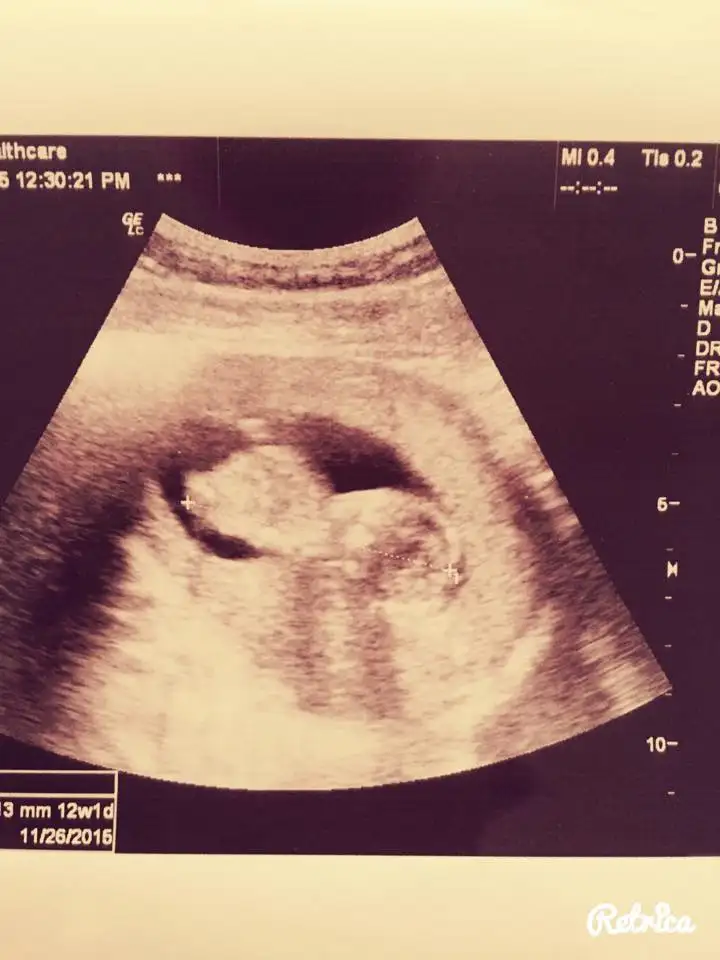

Kızlar bana da yorum yapabilirmisiniz belli oluyor mu bilmiyorum ama açıkçası ben pek anlamıyor bebisim fotoda 12+4 haftalık tüp bebekle oldu sizce cinsiyeti nedir doktor ancak 16. Haftada söyleyebilirim dedi 12 haziranda bir daha ki kontrolüm çok merak ediyorum lütfen yardımcı olun

kızlar merhablar şimdi kontrolden geliyorum nolur bi bakın :))) sizce cinsiyetimiz ne ? 12. haftayı doldurduk bugün

Kızlar bana da yorum yapabilirmisiniz belli oluyor mu bilmiyorum ama açıkçası ben pek anlamıyor bebisim fotoda 12+4 haftalık tüp bebekle oldu sizce cinsiyeti nedir doktor ancak 16. Haftada söyleyebilirim dedi 12 haziranda bir daha ki kontrolüm çok merak ediyorum lütfen yardımcı olunEki Görüntüle 1528009

Bariz belli erkek diyorum ben...belli olunca lutfen yazarsaniz